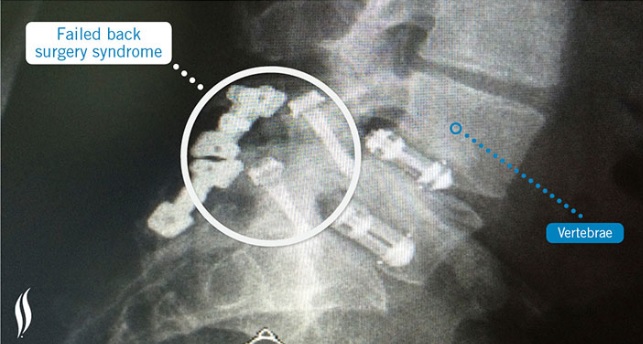

Après chirurgie rachidienne pour prise en charge d'une lombalgie, certains patients vont éprouver des douleurs chroniques : Le syndrome post-laminectomie ou FBSS (Failed Back Surgery Syndrome) décrit ainsi l'état de ces patients aux résultats infructueux après une chirurgie de la colonne vertébrale pour traiter les maux de dos. De plus le taux de succès d'une chirurgie rachidienne diminuant avec les interventions, l'incidence du FBSS augmente donc en conséquence. On estime que jusqu'à 40% des patients qui subissent une chirurgie à dos ouvert souffriront de ce syndrome. Le FBSS tend va toucher plus particulièrement la région lombaire (inférieure) et moins souvent la région cervicale (supérieure) de la colonne vertébrale. Ici, les auteurs estiment, au-delà de l'invalidité et de la diminution de la qualité de vie, l''impact économique de la FBSS de 30.000 à 40 000 € par patient. Etant donnés les taux croissants de chirurgie lombaire et les taux d'échec élevés, l'équipe a cherché à mieux identifier les patients atteints de fibromyalgie avant la chirurgie pour pouvoir les éduquer à la gestion des symptômes. Fibromyalgie et chirurgie orthopédique : Plusieurs études ont montré que les patients atteints de fibromyalgie connaissent moins d'amélioration dans les scores de douleur après procédures orthopédiques comme le remplacement du genou ou de la hanche, cette étude confirme que c'est également le cas après une chirurgie du dos : l'étude, qui a porté sur l'ensemble des patients suivis au Centre médical de l'Université du Vermont de 2010 à 2015, montre en effet une association entre la fibromyalgie et le FBSS très significative avec donc 25% des patients atteints de FBSS ayant un diagnostic de fibromyalgie (voir visuel ci-contre) vs 1,75% en population générale (Source PLoS ONE (1)). Les chercheurs ont quantifié pour chaque patient le nombre total de chirurgies et classé les procédures chirurgicales selon le type.